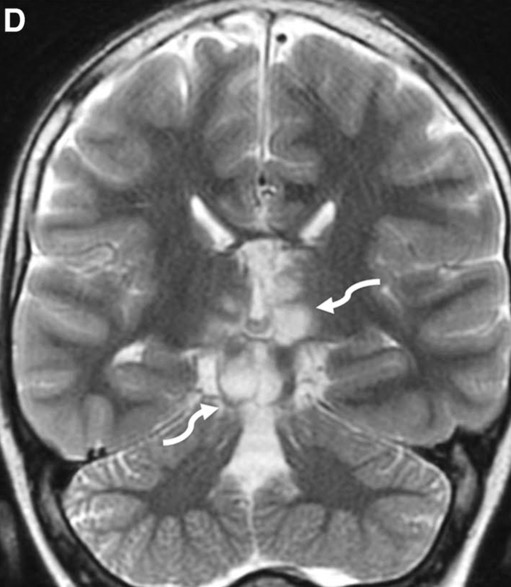

c. Lipomatose encéphalocraniocutanée (ECCL): peau, yeux, SNC)

ECCL: